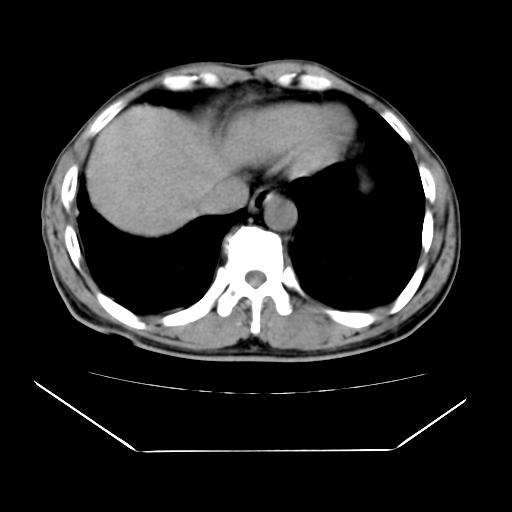

男性,55岁,外院体检afp明显升高,但b超未发现异常,否认乙肝病史。来我院ct增强。有延时扫描。

延时扫描完全充填,血管瘤

肝脏右叶动脉期可见低密度影,至延迟期被充填,考虑血管瘤可能性大。

不排除肝右叶肝癌可能。

如果这个是癌灶的话则下腔静脉有瘤栓可能

肝6段血管瘤

血管瘤可能性大。

考虑肝右静脉影。